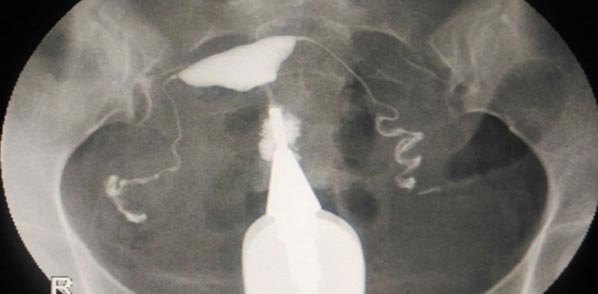

Hysterosalpingogram, HSG

The HSG fertility test provides information about the internal architecture of the fallopian tubes and the uterus.. Dye is passed through a small tube through the cervix and into the uterus. The dye is “radiopaque” meaning that it can be visualized on X-ray.